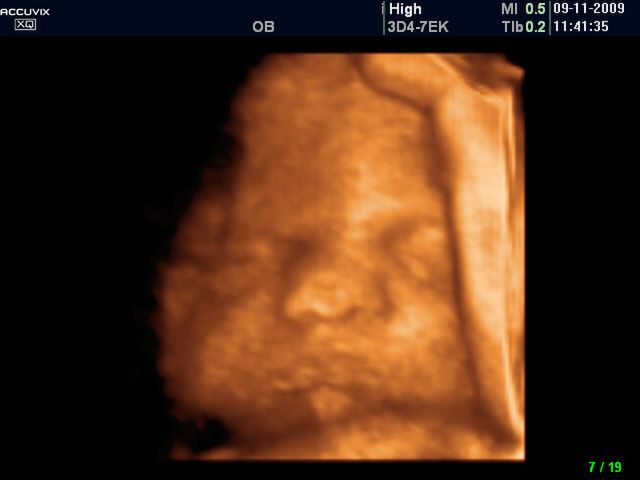

Płód w 40 tygodniu ciąży (zdjęcia 3D)

Nadządy są przygotowane do samodzielnego działania, dziecko jest gotowe do przyjścia na świat